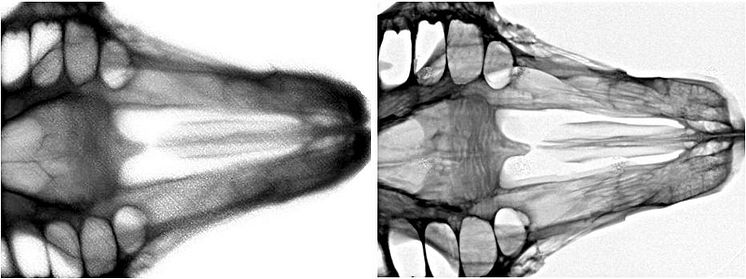

Scint-X, som har sitt ursprung i KTH i Kista, har utvecklat en patenterad scintillatorteknologi till röntgenindustrin som medför att man får en bättre bildkvalitet genom högre upplösning i bilden. Som en kund uttryckt saken ”Med den här scintillator-teknologin, kan man nå nästa nivå vad avser upplösning inom röntgenindustrin. ”

Scint-X utvecklar och marknadsför en teknik för att förbättra prestanda av digitalbaserade röntgendetektorer, baserad på dess patenterade och innovativa teknik för strukturerade scintillatorer. Med Scint-X teknik kan tillverkare av röntgensystem uppnå en oöverträffad bildkvalitet genom mycket hög upplösning.  För mer information besök Scint-X på www.scint-x.com

• Scint-X röntgenteknik